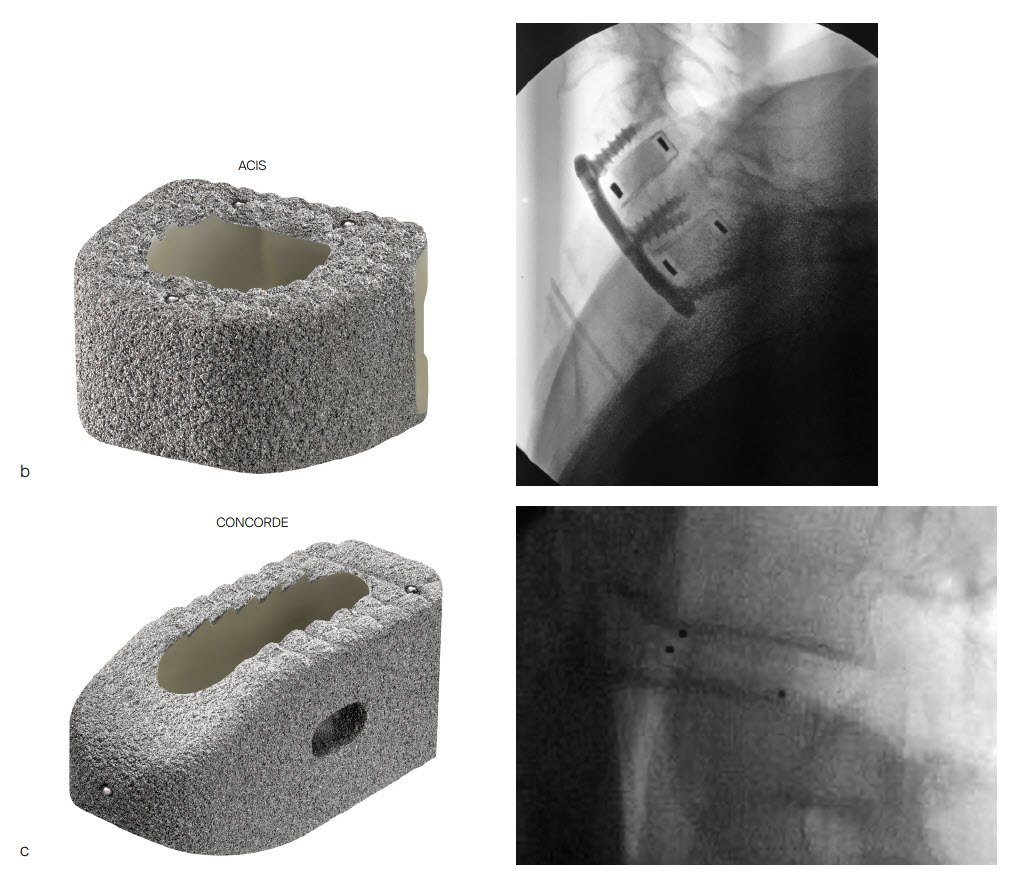

PROTI 360° is a family of integrated titanium interbody cages (Fig 1) that promote spinal fusion, intended for use in patients with degenerative disc disease (DDD). The cage family includes the ACIS PROTI 360° System for cervical fusion, and the T-PAL PROTI 360° System and CONCORDE PROTI 360° Systems for lumbar interbody fusion.

The PEEK core of the PROTI 360° cage has favorable imaging characteristics which support the postoperative assessment of fusion, while the titanium outer layer allows measurement of cage positioning. Clinically, depending on the image quality, plane of view, and patient anatomy, the PROTI 360° cage may show a ghost image of the entire cage on fluoroscopic images (Fig 7). CT images show minimal scatter around the implant (Fig 8).

The PROTI 360 cages are available as sterile implants and are compatible with ACIS System (Fig 9a), T-PAL Interbody System (Fig 9c) and CONCORDE Bullet (Fig 9c) instrument sets. The ACIS implants are available in 5-10mm heights, in Lordotic Small, Standard, and Large designs and in Parallel Standard or Convex Standard. The CONCORDE implants are available in Parallel and Lordotic designs (7-15 mm heights, 23 and 27 mm lengths). The T-PAL implants are available in the High Curve design (7-15 mm heights, 10 x 28, 12 x 32 footprints).